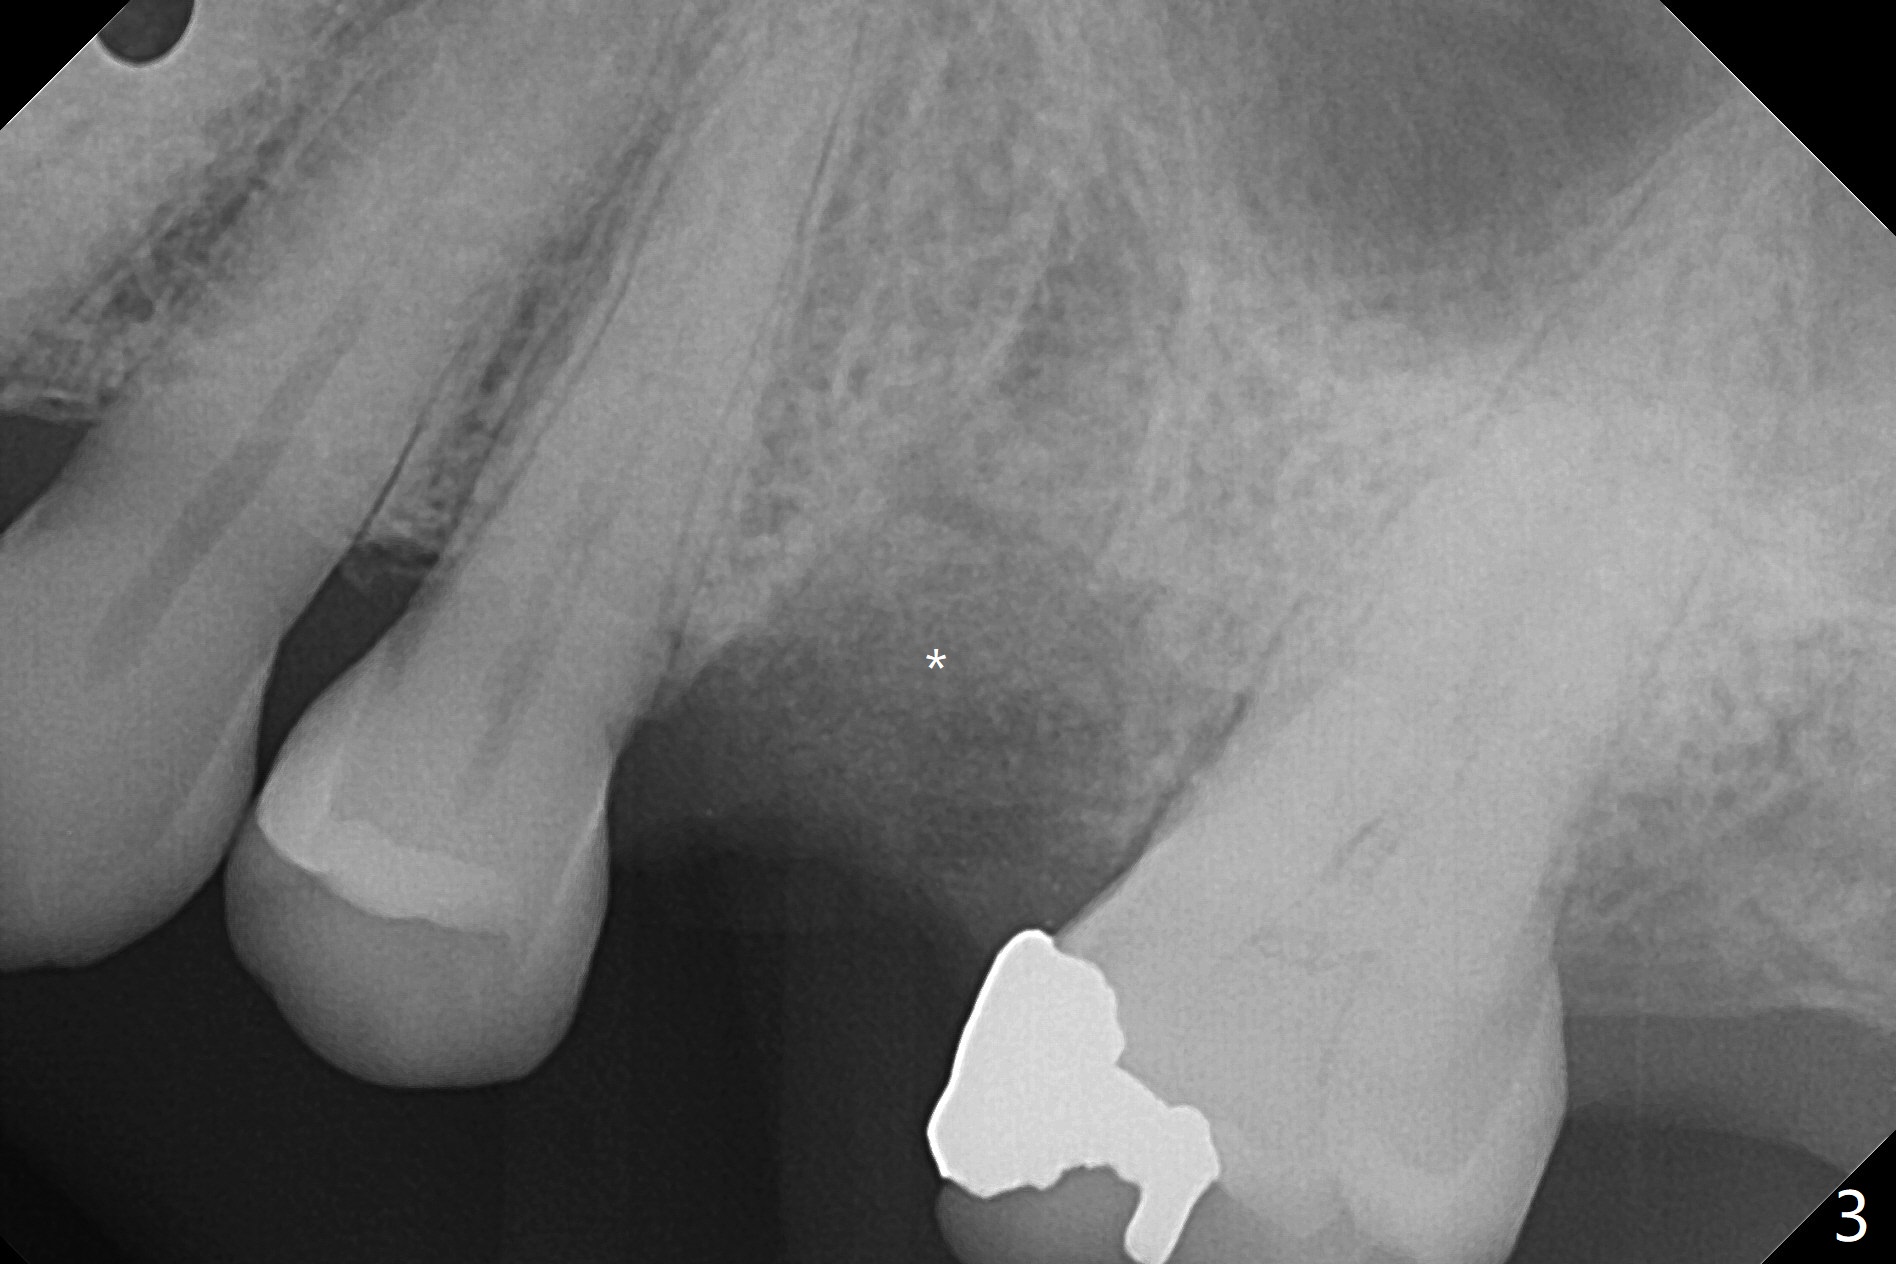

A 65-year-old woman cracks the tooth #13 (Fig.2) while the implants placed at #2 and 3 in her home country are osteointegrating (Fig.1). Extraction turns out to be surgical; after removing the curved root, the socket is large. Osteogen plug is placed for socket preservation due to finance (Fig.3 *). While the socket has healed, the buccal plate has collapsed 2 months postop (Fig.4).